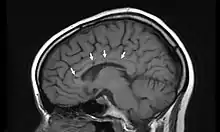

IRM d'une patiente atteinte du syndrome de Susac montrant les « trous » du corps calleux associés à la régression des symptômes (flèches).

L'IRM cérébrale montre des anomalies de la substance blanche ainsi qu'au niveau du corps calleux[4].